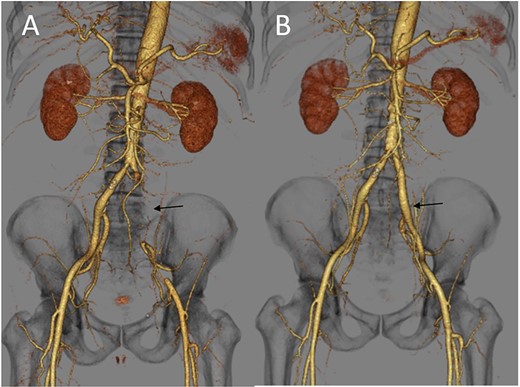

A 62-year-old man with aggravated symptoms of fever, cough and malaise for 12 days was admitted to the hospital. The patient was obese, with a body mass index of 30.0. The patient was conscious but presented with laboured breathing. His body temperature was 36.7 C, blood pressure was 121/62 mmHg, heart rate was 84/min respiratory rate was 24/min and oxygen saturation was 82% with room air. Non-enhanced computed tomography (CT) showed inflammation in the total lung field (Fig. 1A). Blood test results revealed increased levels of D-dimer of 23.4 mg/L, C-reactive protein of 1600 nmol/L and creatinine of 150.3 μmol/L. The result of SARS-CoV-2 polymerase chain reaction detective kit (TAKARA BIO INC., Shiga, Japan) was positive with N501Y mutation. He was subsequently admitted to the hospital and received oxygen inhalation and intravenous injections of remdesivir, dexamethasone and unfractionated heparin. On the following day, the patient complained of pain and cold sensation in his left leg upon waking. Emergency enhanced CT showed a thrombus in the aorta at the juxtarenal level (Fig. 1B) and an obstructed left iliac artery with a thrombus (Fig. 2A). No cardiac thrombi were observed. The activated partial thromboplastin time was 28 s, and the D-dimer level was unchanged from the previous day, as shown in Fig. 3. Other blood test results showed normal values, including antinuclear antibodies and markers of vasculitis or malignancy.

(A) Three-dimensional enhanced CT image obtained immediately after developing acute limb ischemia. The left iliac artery was occluded as indicated by an arrow. (B) Three-dimensional enhanced CT image obtained on post-operative day 11. A patent left iliac artery was observed, as indicated by an arrow.

The patient underwent urgent thrombectomy to salvage the left lower limb. Using a Fogarty catheter, fresh thrombus in the left iliac artery and superficial femoral artery was removed. The patient’s hypoxia condition continued until post-operative day 4. From post-operative day 6, coumadin was initiated to treat the remaining thrombus in the aorta (Fig. 1C). After confirming a negative test result for COVID-19, the patient was discharged on post-operative day 20. A month after the surgery, repeat enhanced CT showed a decrease in the quantity of intra-aortic thrombus (Fig. 1D) and the patent left iliac artery (Fig. 2B).